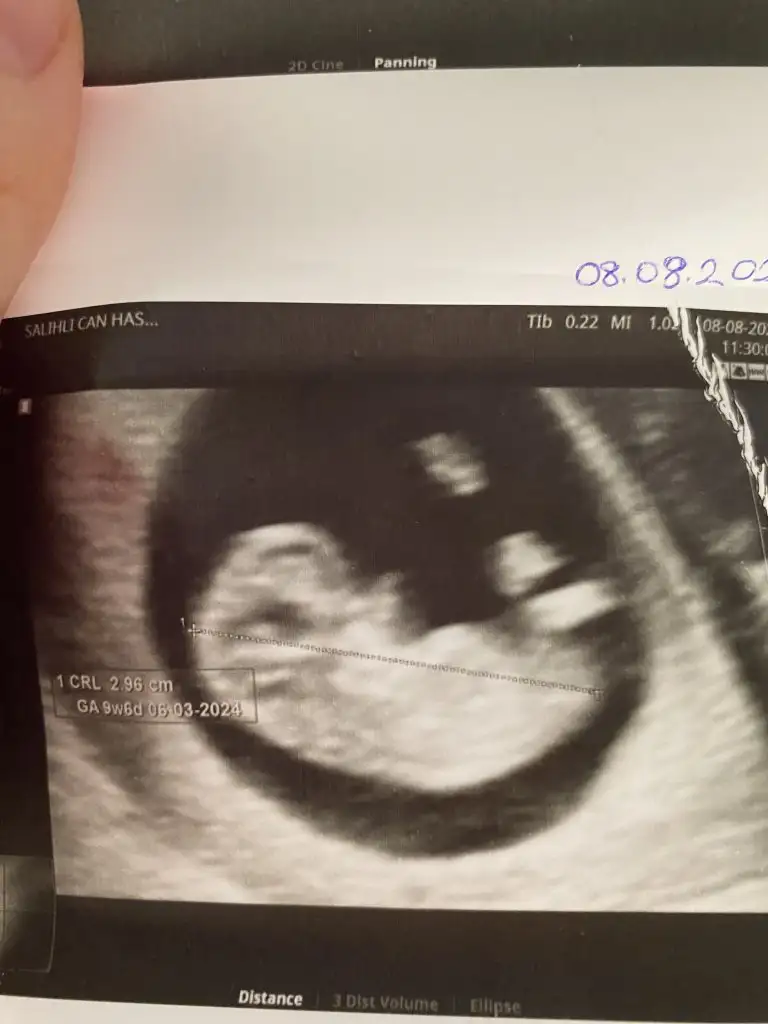

Benim bebeğimi de yorumlar mısınız rica etsem. Ultrason görüntülerim pek net değil ama sırasıyla 6 -9 - 12 haftalkk ekliyorum. Teşekkür ediyorum şimdiden N Nakafile

Kız bebeğine benziyor. Hayırlısı ile gelsin. Öğrenince yazarsınız bakalım doğru tahmin mi olacak. Nub kısmı düz çünkü bebeğin